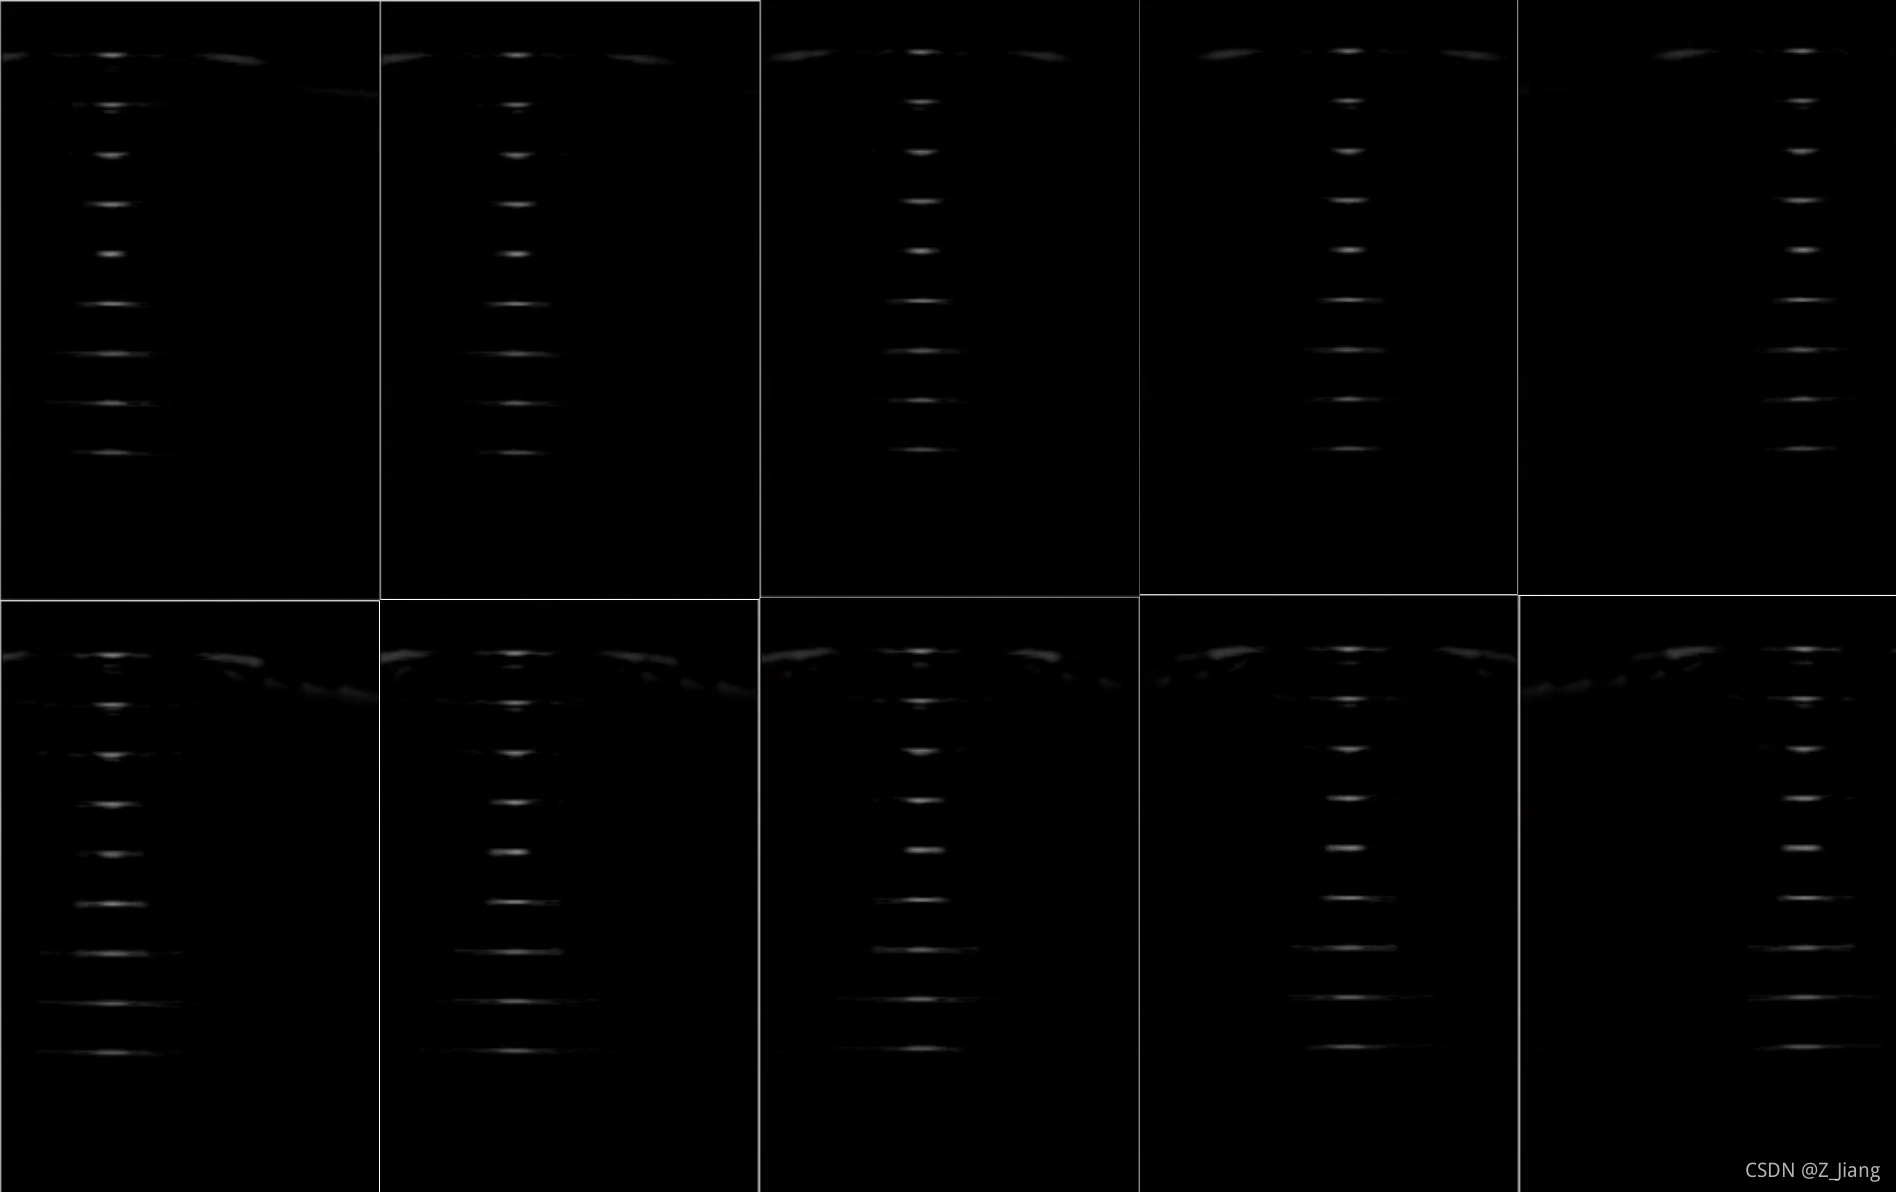

平移探头动的画

如果视频点不开,还是看下面不动画,自己脑补动起来

上排:NO MLA(MLA=1) 下排:MLA=4

我们可以看到MLA=4,在相对运动时,靶点明显忽宽忽窄,扭来扭去,这就是我上面提到的第二点,也经常叫做MLA block artifact;而在MLA=1,在相对运动时,靶点时稳定的(除了在探头边上,由于接收孔径不对称造成少量轻微扭曲);